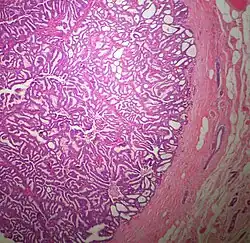

Pathology

.jpg)

The microscopic histopathology (refer to adjacent high-power photomicrograph) of EPC tissues typically shows papillary structures with fibrovascular cores and proliferating neoplastic epithelial cells growing within cystic spaces, all of which are enclosed within a dense fibrous capsule. In general, EPC tumors do not have areas of neuroendocrine degeneration or myoepithelial cells.[6] The presence of a dense fibrous capsule distinguishes EPC from other papillary breast tumors, particularly PDCIS;[3] the absence of neuroendocrine differentiation areas helps distinguishes EPC from SPC tumors;[3] and the absence of peripherally located myoepithelial cells helps distinguish EPC from PDCIS tumors.[7] EPC tumors may be totally contained within their fibrous capsules or have one or more areas that have invaded through the capsule to normal breast tissues and/or chest muscles; these two variants are termed in situ EPC and infiltrative EPC, respectively.[3][5] In a study of 25 individuals with EPC, 14 had in situ and 11 had invasive disease with 6 of the invasive tumors rated as high grade (see high grade tumors) based on their microscopic histopathology.[5] Rarely, EPC tumors metastasize to nearby sentinel lymph nodes, other nearby axillary lymph nodes, and/or distant tissues; these metastases have in general shown papillary morphologic features similar to their primary tumors.[6] Uncommonly, EPC tumors co-exists with nearby PDCIS,[7] invasive carcinoma of no special type, invasive cribriform carcinoma of the breast, mucinous carcinoma, or tubular carcinoma[3] tumors.